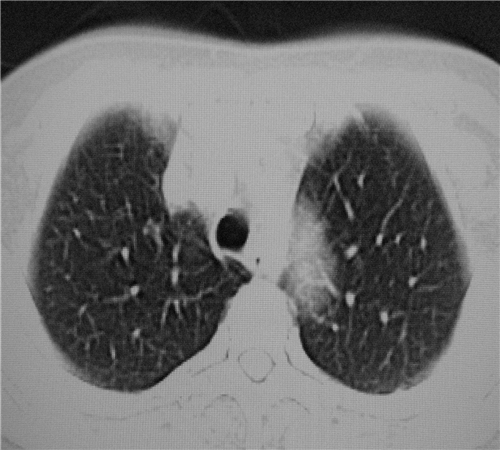

标题: CT26849:女67岁反复胸痛两天余,临床考虑夹层。 [打印本页]

标题: CT26849:女67岁反复胸痛两天余,临床考虑夹层。

1)右肺感染性病变。2)建议行ct增强扫描或mri检查排除主动脉夹层。

双下肺感染,右侧显著。有无夹层,增强扫描后再诊断。

1.考虑双肺感染,右侧为重;2.建议ct增强或mri排除主动脉夹层

平扫未见确切夹层征,建议必要时增强扫描或mri检查。